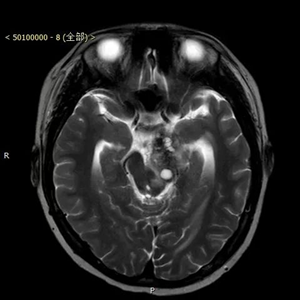

患者,男,入院时间2016年8月9日,入院时年龄13岁5月24天。主诉:右腿晃动3个月,伴右侧肢体力量减弱2个月。术后病理显示为囊性成熟型畸胎瘤,肿瘤组织内神经胶质细胞成分、平滑肌及腺上皮成分细胞异质性明显。

患者来到北京儿童医院就医时,由于肿瘤压迫脑功能区导致了瘫痪。北京儿童医院神经外科葛明教授及团队,对其进行了全切除手术,肿瘤直径4公分左右,手术路径深十公分左右,分块切除,历时四小时完整切除。术后患者瘫痪状态消失,随访恢复良好。

患者术后资料(下图)